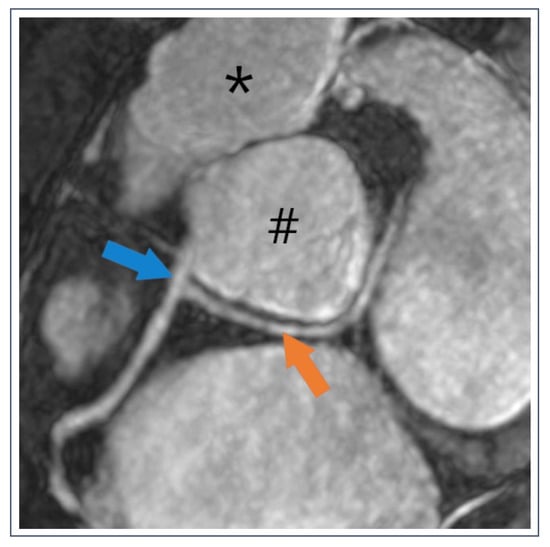

3. Hinge Point Fibrosis—Bad Actor or Innocent Bystander?

- Chan, R.H.; Maron, B.J.; Olivotto, I.; Assenza, G.E.; Haas, T.S.; Lesser, J.R.; Gruner, C.; Crean, A.M.; Rakowski, H.; Rowin, E.; et al. Significance of Late Gadolinium Enhancement at Right Ventricular Attachment to Ventricular Septum in Patients with Hypertrophic Cardiomyopathy. Am. J. Cardiol. 2015, 116, 436–441. [Google Scholar] [CrossRef]

- Ding, W.Y.; Cooper, R.M.; Hasleton, J.; McKay, V.; Modi, S. Ventricular Hinge Point Fibrosis as a Pathological Marker of Hypertrophic Cardiomyopathy in the Absence of Significant Left Ventricular Hypertrophy? Can. J. Cardiol. 2016, 32, 1577.e13–1577.e14. [Google Scholar] [CrossRef] [PubMed]

- Grigoratos, C.; Pantano, A.; Meschisi, M.; Gaeta, R.; Ait-Ali, L.; Barison, A.; Todiere, G.; Festa, P.; Sinagra, G.; Aquaro, G.D. Clinical importance of late gadolinium enhancement at right ventricular insertion points in otherwise normal hearts. Int. J. Cardiovasc. Imaging 2020, 36, 913–920. [Google Scholar] [CrossRef] [PubMed]